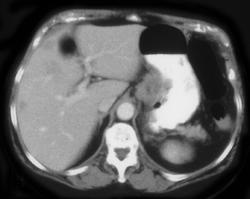

Subtle Gastric Cancer With Nodes in the Porta